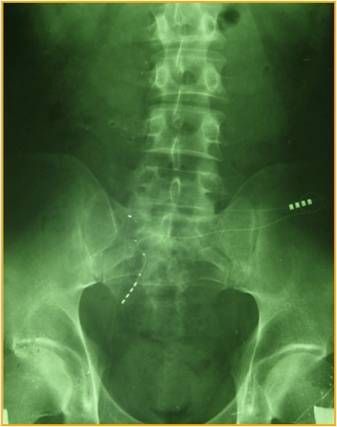

Техника и основные принципы установки электродов те же, что и при спинальной стимуляции. Однако, учитывая каудальное направление установки, такой метод ещё называют ретроградной установкой электродов. В классическом описании методики под контролем ЭОП ретроградно выполняется пункция S3-S4 межпозвонкового отверстия с проведением электрода по ходу сакрального корешка.

Расчет точек пункции

Коррекция под рентгенконтролем

Техника ретроградной установки электрода (MEDTRONIC)

Установка электрода